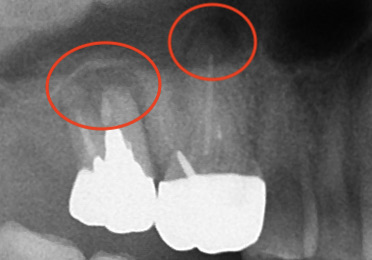

こちらはデンタルX線写真

赤丸の部分。根尖病巣によって黒くなっており、骨が溶けていて炎症が見られます。

揺れているのは一番奥でしたが。

両方根管治療した方が良さそうですね。

6年後はだいぶ根尖部にも骨ができてくれています。

7番の根分岐部(奥歯は根っこが複数あり、その股の部分)の

黒い部分は歯周病による骨の吸収なので仕方ありません。